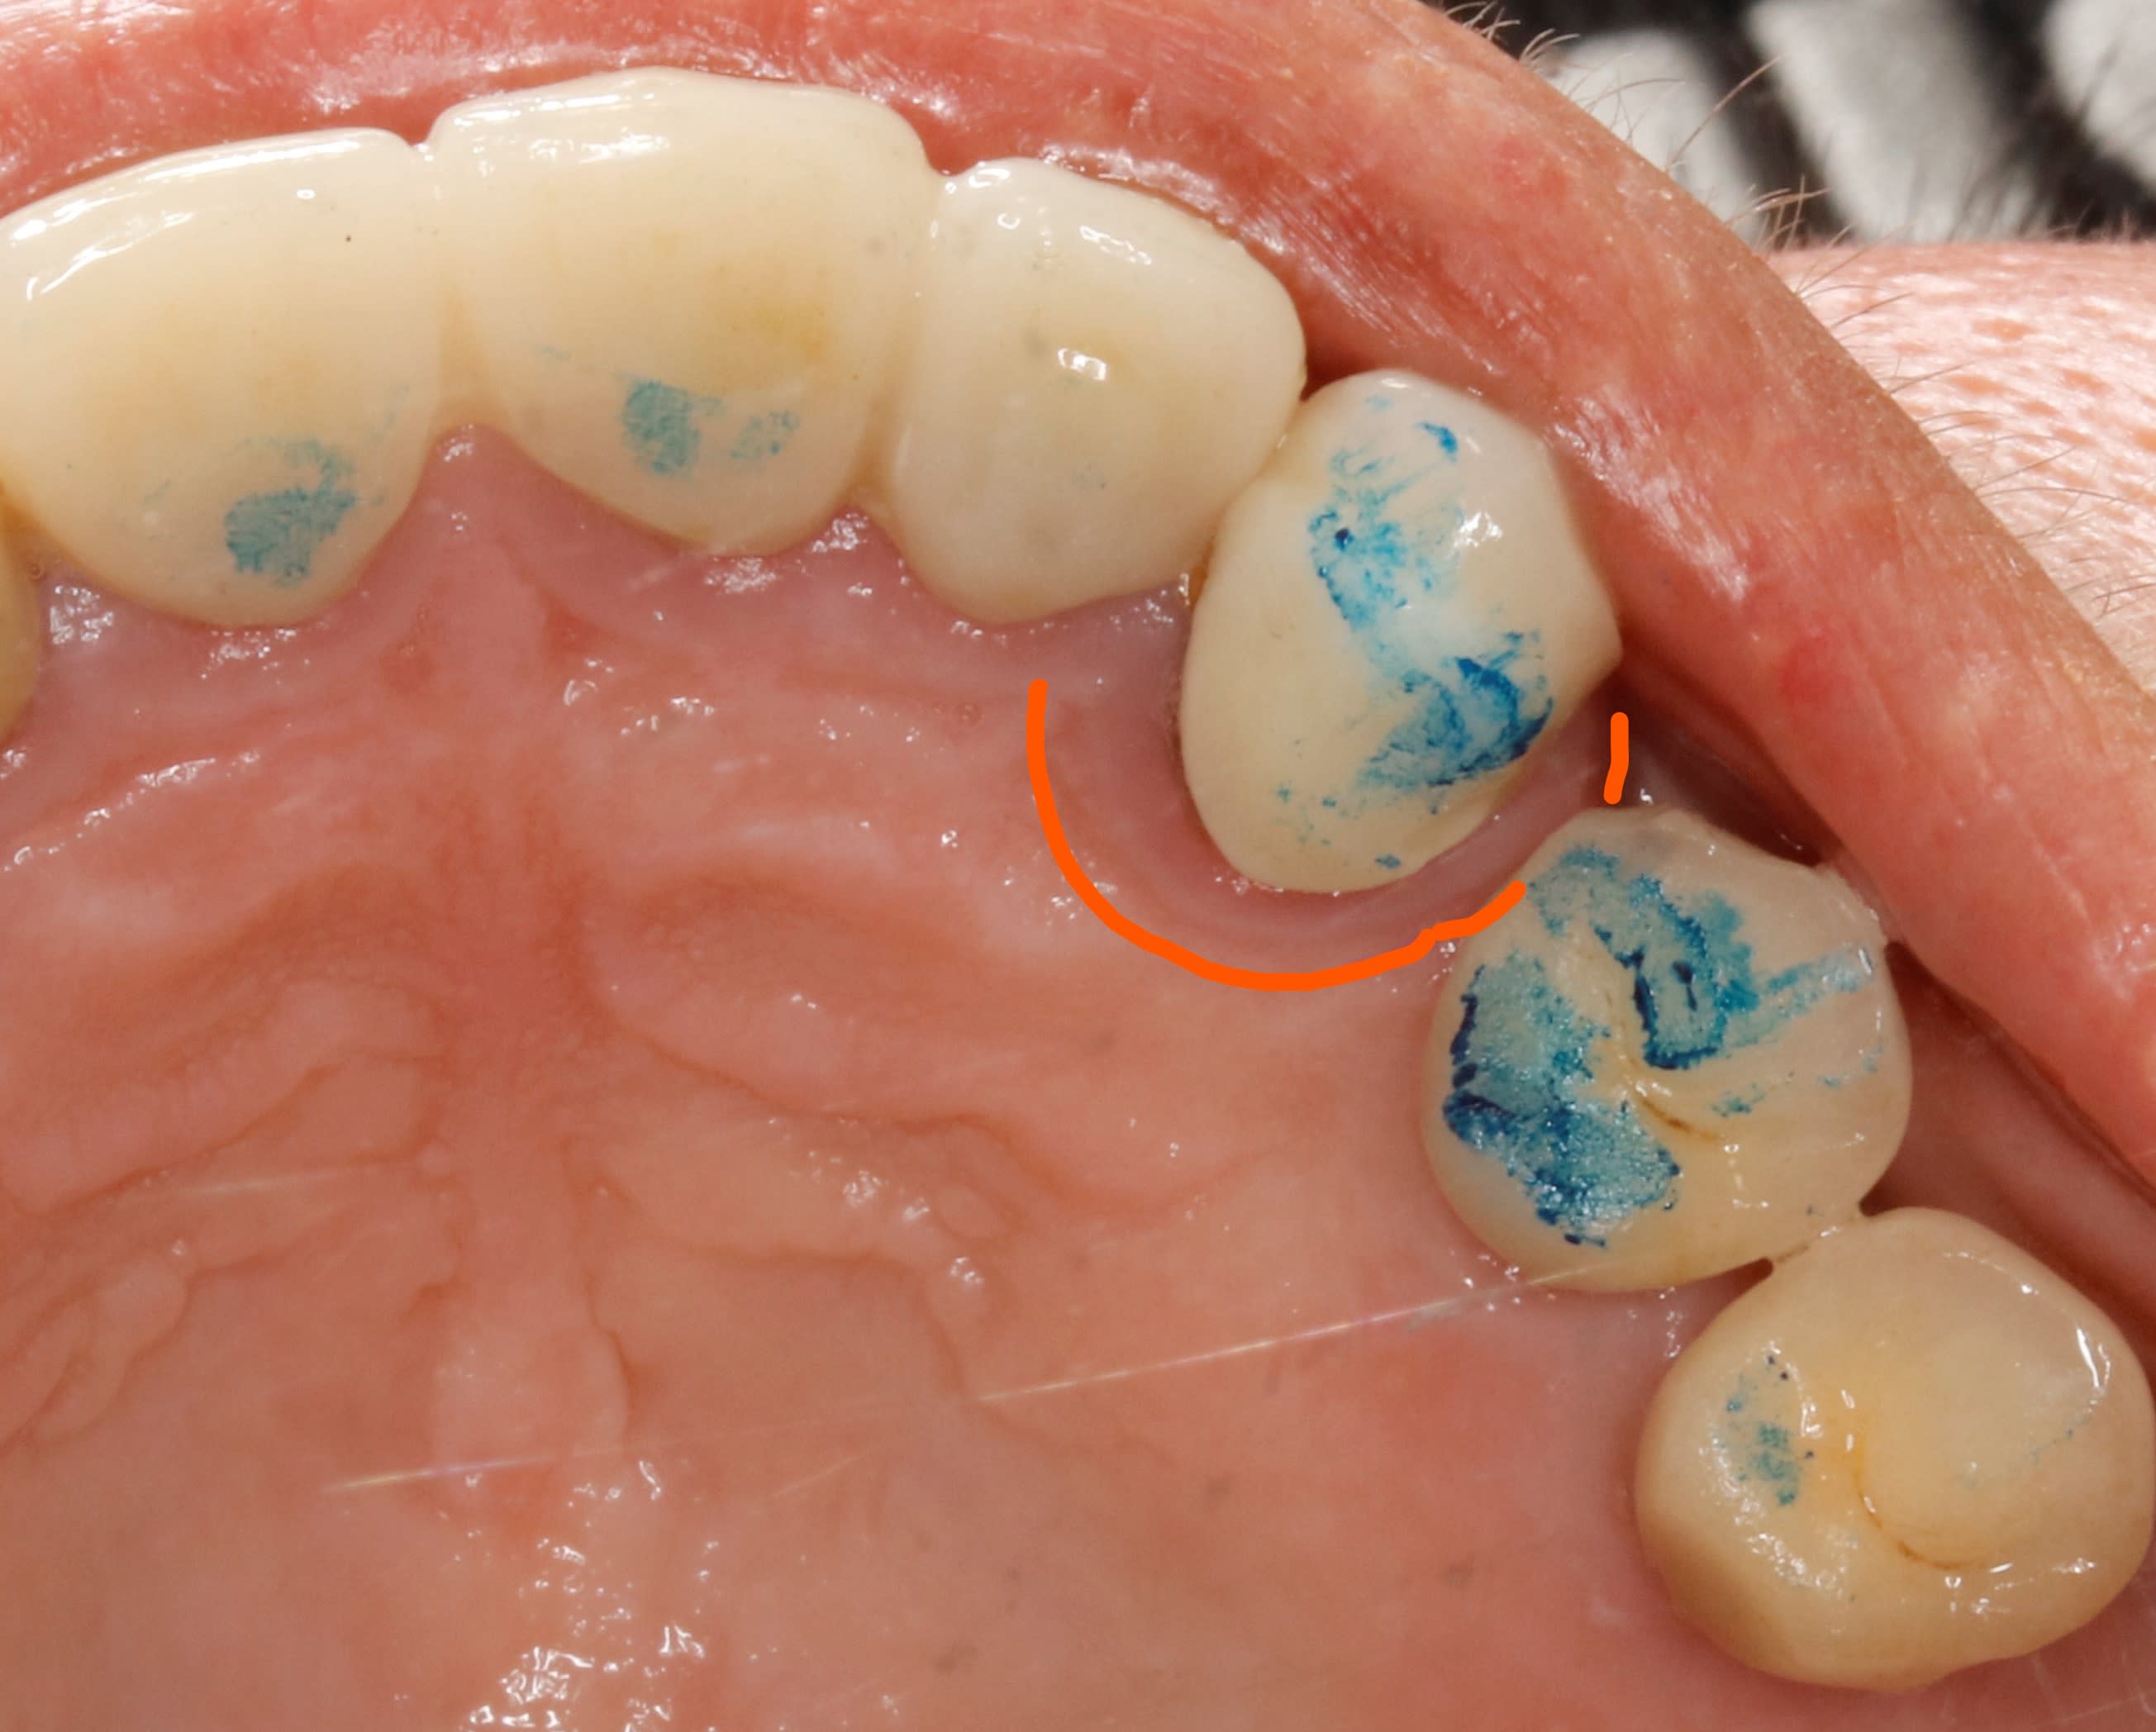

aller pour 500 balles de moins .

quand je vois ça ça m interpelle : viens mon petit viens , viens me limer :-)

Inkedqgeoud6z4ayshtqdkufi li slcymy - Eugenol

PtnbZ

01/10/2020 à 19h34

Tu ne nous dis pas tout vieux filou. La patiente quand elle mord elle a un glissement avant d'arriver dans son occlusion habituelle?

Si elle a cassé sa 23 comme ça, c’est qu’avec la fermeture elle fait une latéralité à gauche ou une propulsion.

D’instinct je dirais que le point mesial sur la 44 n’a pas à être la :))